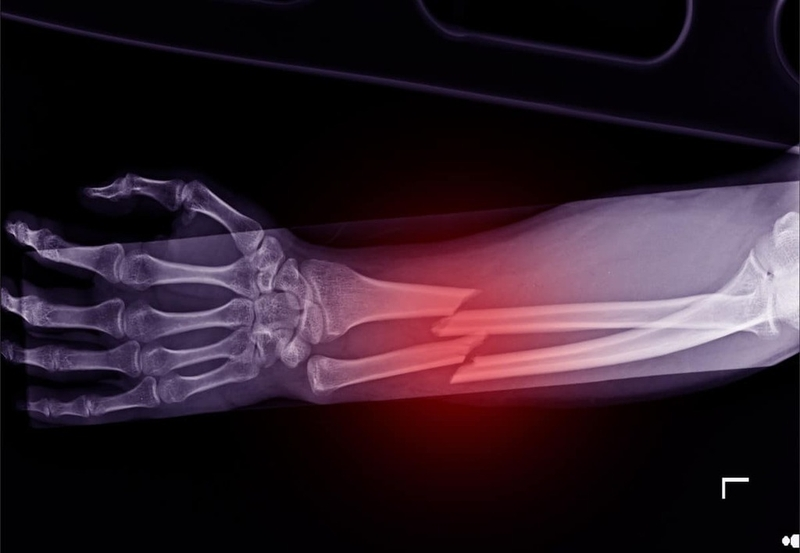

Xương còn mềm và đàn hồi tốt: Xương trẻ nhỏ đang trong quá trình tăng trưởng nên có cấu trúc mềm hơn, nhiều lỗ xốp và giàu chất nền. Nhờ đó, xương có thể chịu được uốn cong và nén ép tốt hơn, ít bị gãy vụn như xương người lớn. Một số trường hợp xương còn có khả năng tự chỉnh thẳng sau biến dạng nhẹ.

Tổn thương sụn tăng trưởng thường ít nghiêm trọng: Khi trẻ bị gãy xương, phần sụn tiếp hợp (sụn tăng trưởng) – yếu tố quyết định chiều dài và hình dạng xương – chỉ bị ảnh hưởng khoảng 10–15%. Đồng thời, gãy vụn xương ở trẻ rất hiếm gặp, giúp quá trình liền xương diễn ra thuận lợi hơn.

Khả năng tự kích thích phục hồi mạnh mẽ: Ổ gãy xương ở trẻ có khả năng kích thích tăng sinh tế bào xương mới rất tốt nhờ lưu lượng máu tăng mạnh đến vùng sụn tiếp hợp. Điều này giúp xương nhanh chóng hình thành can xương và liền lại tự nhiên.

Cốt mạc dày, liên tục và giàu mạch máu: Cốt mạc (lớp màng bao quanh xương) của trẻ dày, còn nguyên vẹn và được nuôi dưỡng bởi hệ thống mạch máu phong phú. Đây là yếu tố quan trọng giúp xương trẻ liền nhanh và chắc hơn so với người lớn.

Tuổi càng nhỏ, tốc độ liền xương càng nhanh: Trẻ sơ sinh có thể liền xương chỉ sau 2–3 tuần; trẻ từ 7–10 tuổi thường mất khoảng 6 tuần; còn trẻ trên 10 tuổi khoảng 8–10 tuần. Trong khi đó, người lớn cần thời gian dài hơn nhiều cho cùng một mức độ tổn thương.